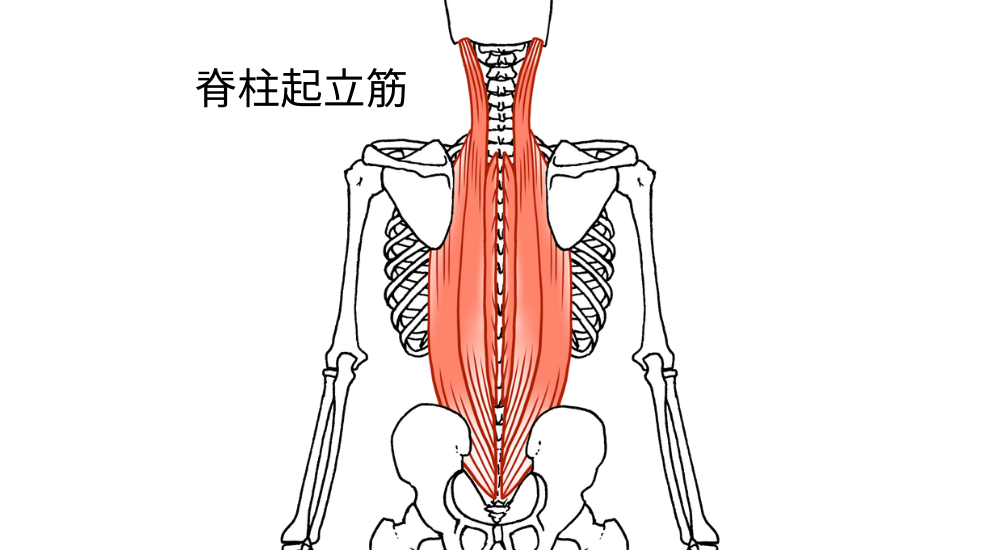

- 脊柱起立筋(特に胸部): 背骨に沿った筋肉。猫背で引き伸ばされて硬くなり、背中の張りや痛みの原因となります。

- 脊柱起立筋(特に腰部): 腰の背骨に沿った筋肉。反り腰で常に緊張・短縮しやすく、腰痛の大きな原因となります。